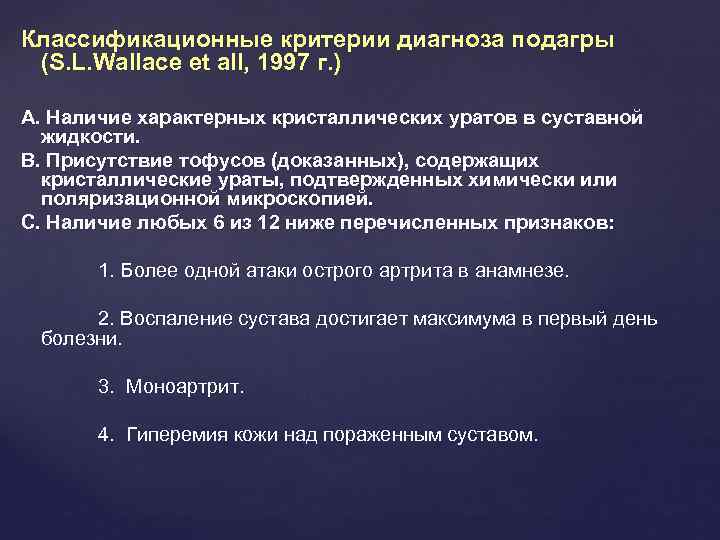

Классификационные критерии диагноза подагры (S. L. Wallace et all, 1997 г. ) А. Наличие характерных кристаллических уратов в суставной жидкости. В. Присутствие тофусов (доказанных), содержащих кристаллические ураты, подтвержденных химически или поляризационной микроскопией. С. Наличие любых 6 из 12 ниже перечисленных признаков: 1. Более одной атаки острого артрита в анамнезе. 2. Воспаление сустава достигает максимума в первый день болезни. 3. Моноартрит. 4. Гиперемия кожи над пораженным суставом.

Классификационные критерии диагноза подагры (S. L. Wallace et all, 1997 г. ) А. Наличие характерных кристаллических уратов в суставной жидкости. В. Присутствие тофусов (доказанных), содержащих кристаллические ураты, подтвержденных химически или поляризационной микроскопией. С. Наличие любых 6 из 12 ниже перечисленных признаков: 1. Более одной атаки острого артрита в анамнезе. 2. Воспаление сустава достигает максимума в первый день болезни. 3. Моноартрит. 4. Гиперемия кожи над пораженным суставом.

Классификационные критерии диагноза подагры (S. L. Wallace et all, 1997 г. ) 5. Припухание и боль в первом плюснефаланговом суставе. 6. Одностороннее поражение первого плюснефалангового сустава. 7. Одностороннее поражение суставов стопы. 8. Подозрение на тофусы. 9. Гиперурикемия (? ) 10. Ассиметричный отек суставов (рентгенография). 11. Субкортикальные кисты без эрозий (рентгенография). 12. Отрицательные результаты при посеве синовиальной жидкости. Наличие 6 и более признаков подтверждает диагноз подагры. Наиболее достоверны такие признаки, как острый или, реже, подострый артрит, обнаружение уратов в синовиальной жидкости и наличие доказанных тофусов. Диф. диагноз: -псевдоподагра; септический артрит; реактивный артрит; ревматоидный артрит

Классификационные критерии диагноза подагры (S. L. Wallace et all, 1997 г. ) 5. Припухание и боль в первом плюснефаланговом суставе. 6. Одностороннее поражение первого плюснефалангового сустава. 7. Одностороннее поражение суставов стопы. 8. Подозрение на тофусы. 9. Гиперурикемия (? ) 10. Ассиметричный отек суставов (рентгенография). 11. Субкортикальные кисты без эрозий (рентгенография). 12. Отрицательные результаты при посеве синовиальной жидкости. Наличие 6 и более признаков подтверждает диагноз подагры. Наиболее достоверны такие признаки, как острый или, реже, подострый артрит, обнаружение уратов в синовиальной жидкости и наличие доказанных тофусов. Диф. диагноз: -псевдоподагра; септический артрит; реактивный артрит; ревматоидный артрит